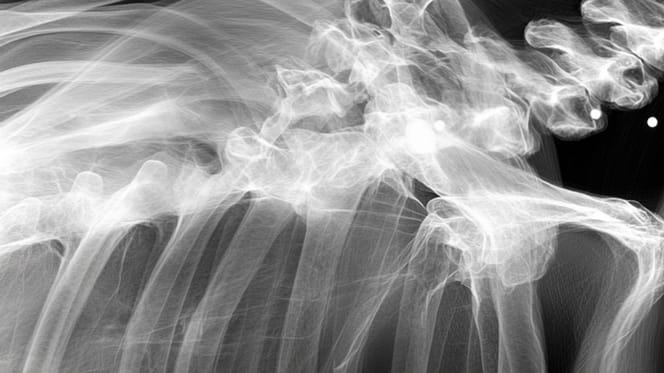

Algunos años después de la adopción, el propietario de Momo se llevó una desagradable sorpresa al acudir al veterinario para hacerle una simple radiografía. La perra empezaba a tener dificultades para moverse.

La radiografía reveló que, con toda probabilidad, había sido utilizada para la cría intensiva. Pero eso no era todo. Además de sufrir artritis y displasia de cadera, Momo escondía un secreto aún más inquietante.

El veterinario también descubrió que la perra había sido tiroteada en el pasado. Una de las balas había pasado muy cerca de la columna vertebral. Por suerte, ninguna de ellas tuvo consecuencias irreversibles en su vida.